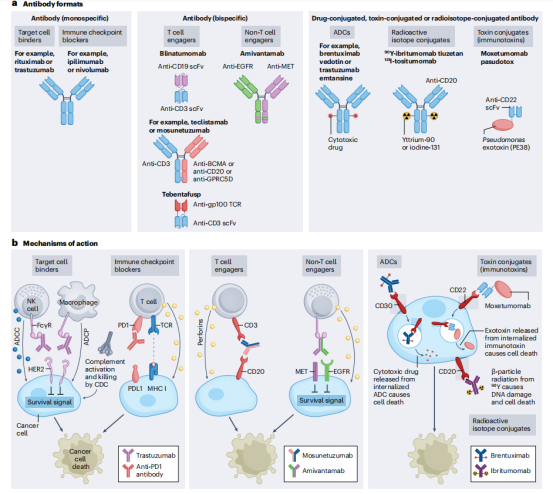

抗体疗法根据其结构和功能机制可以分为三种主要形式,单特异性抗体,双特异性抗体,和结合有效载荷(如药物,毒素,放射性药物)的抗体。这些不同类型和机制的抗体提供了多种策略来靶向和杀死癌细胞,每种方法都有其独特的优势和潜在的应用前景,为癌症治疗带来了新的希望。

单特异性抗体是与靶抗原结合的全长免疫球蛋白,它有5种亚型IgG、IgM、IgA、IgE和IgD,其中只有IgG4与新生儿Fc受体(FcRn)结合,导致半衰期长约21天。大多数FDA和EMA批准的抗体以及正在开发的抗体使用IgG抗体格式,IgG抗体有四个亚类(IgG1、IgG2、IgG3和IgG4),大多数治疗性抗体利用IgG1亚类。单特异性抗体一般靶向抗原是细胞表面蛋白,主要是在实体癌中过表达的生长因子受体,对于血液系统恶性肿瘤,抗体通常针对由不同免疫细胞亚群表达的细胞表面糖蛋白(也称为分化簇(CD)标记物)。

单特异性抗体结合癌细胞上的抗原,通过多种机制导致细胞死亡,包括生长因子受体(如人表皮生长因子受体2(HER2))的生存信号中断,免疫细胞的激活(如自然杀伤(NK)细胞介导的抗体依赖性细胞毒性(ADCC)和巨噬细胞介导的抗体依赖性细胞吞噬(ADCP))。以及通过激活补体级联反应(补体依赖性细胞毒性(CDC))。免疫检查点阻断抗体结合并激活免疫细胞,如T细胞导联致免疫介导的癌细胞死亡。

双特异性抗体可以结合两种不同的抗原或表位,抗原既可以定位在同一靶细胞上,也可定位在不同靶细胞上,针对两种不同细胞的双特异性抗体大多是T细胞连接物,将癌细胞与效应细胞交联,称为T细胞接合器(TCE)双特异性抗体。交联后,效应T细胞被激活,通过释放细胞毒性颗粒和淋巴因子来杀死结合的靶癌细胞。另一类双特异性抗体参与由同一靶细胞表达的不同抗原,例如两种不同的生长因子受体。这种双特异性抗体通过阻断通过目标生长因子受体的增殖信号,以及激活NK细胞和巨噬细胞来杀死癌细胞,从而杀死目标细胞。

Blinatumomab由双特异性抗体所需的最小元素组成;一种靶向癌症的scFv(抗CD19)。Blinatumomab通过抗CD19scFv作用于B细胞,同时通过抗CD3scFv连接和激活T细胞,导致B细胞死亡。Blinatumomab在一系列B细胞恶性肿瘤中显示出活性,并被批准用于治疗B细胞前体急性淋巴细胞白血病(B-ALL)。

双特异性抗体也被设计用于结合目标癌细胞上的两种不同抗原或表位,而不涉及效应T细胞。它们的抗癌作用是通过阻断两种增殖信号通路介导的,从而最大限度地发挥抗肿瘤活性。除了它们的受体阻断活性外,这些双特异性抗体也可以被设计成含有一个功能性的IgG1Fc结构域,使它们能够通过非T细胞免疫效应途径(如ADCC、ADCP和CDC)杀死癌细胞。Amivantamab是第一个靶向癌细胞表达的EGFR和MET的受体阻断双特异性抗体被批注用于治疗非小细胞肺癌,Amivantamab的IgG1Fc结构域被设计成低聚焦水平,从而增强FcγRIIIa结合和NK细胞介导的ADCC。TCE双特异性抗体会引起细胞因子释放综合征(CRS)和神经毒性,受体阻断双特异性抗体不能激活T细胞,一般不会诱导CRS和神经毒素。

偶联抗体包括抗体药物偶联物(ADC),免疫毒素,放射性同位素相关联的抗体,这些抗体增强了抗体杀死细胞的能力。ADC是通过将肿瘤靶向抗体与细胞毒性药物连接而构建的。ADC分子与细胞表面抗原结合导致其内化,然后在细胞内释放细胞毒性药物。这允许选择性地将细胞毒性药物递送到癌细胞,同时保留大多数健康组织。ADC的关键成分包括肿瘤靶向抗体、细胞毒性药物和连接抗体与细胞毒性药物的连接体。部分ADC药物已显示出显著的临床成功,选择性地向癌细胞递送强效细胞毒性药物。